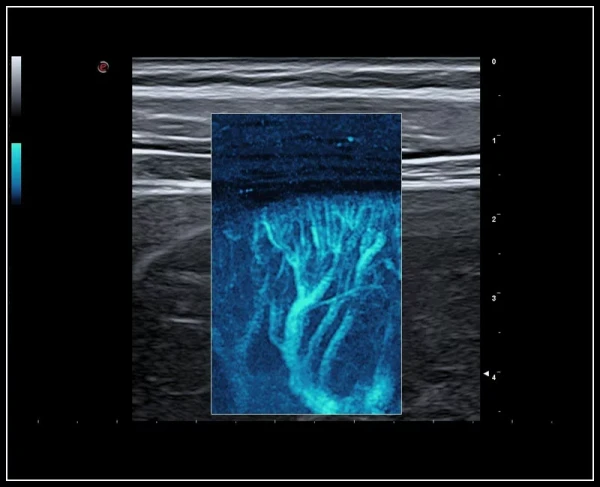

QPack. Doppler rejimlarida va CnTI kontrastli tasvirlash texnologiyasidan foydalangan holda kontrast agenti perfuziyasini miqdoriy baholash uchun yangi vosita